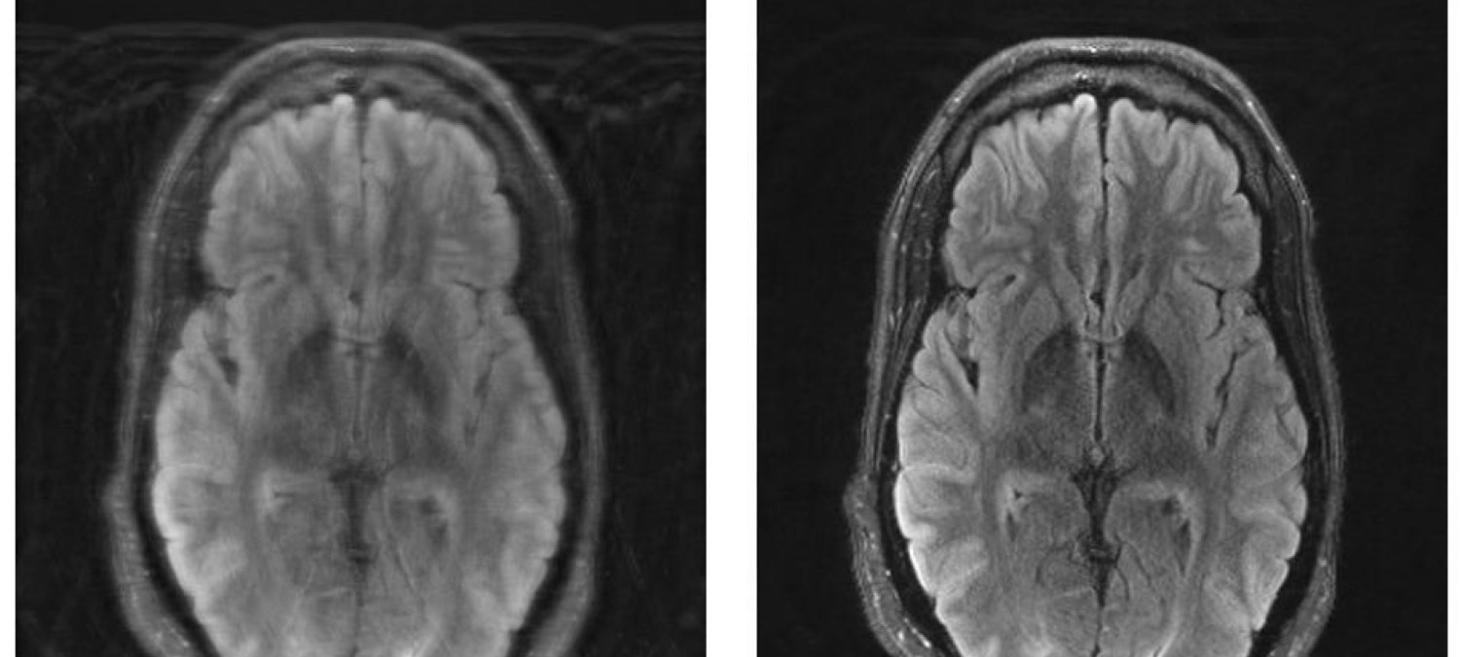

MIT researchers combine deep learning and physics to fix motion-corrupted MRI scans

The challenge involves than just a blurry JPEG. Fixing motion artifacts in medical imaging requires a more sophisticated approach.

news.mit.edu